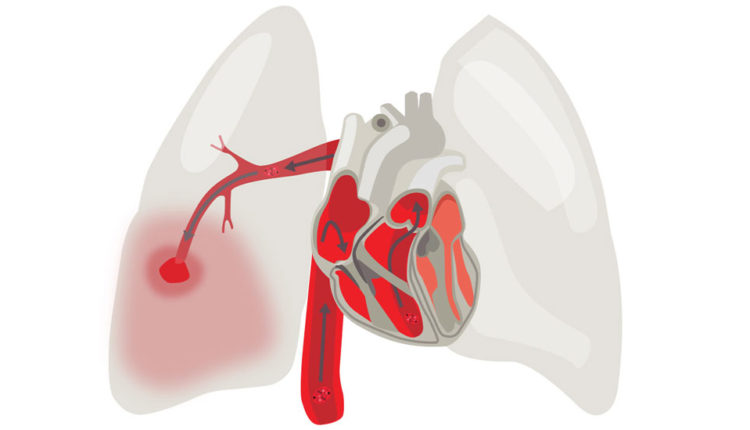

آمبولی ریه، انسداد در یکی از عروق در ریه است. آمبولی ریه در اکثر موارد توسط لختههای خونی ایجاد میشود که از پاها یا بهندرت سایر قسمتهای بدن به سمت ریهها حرکت میکنند (ترومبوز ورید عمقی).

ازآنجاکه این لختهها جریان خون به ریه ها را مسدود میکنند، آمبولی ریه میتواند بسیار خطرناک باشد. با اینحال درمان سریع، خطر مرگ را تا حد زیادی کاهش میدهد. انجام اقدامات لازم برای پیشگیری از ایجاد لختههای خون در پاها به محافظت از شما در برابر آمبولی ریه کمک خواهد کرد.

آمبولی ریه زمانی اتفاق میافتد که یک توده از مواد – اغلب یک لختهی خون – داخل یک شریان گیر میکند. این لختههای خون اغلب از وریدهای عمقی پاها میآیند. این عارضه به ترومبوز ورید عمقی (DVT) معروف است.

در بسیاری از موارد، لختههای متعدد در آمبولی ریه دخیل هستند. بخشهایی از ریه که توسط شریانهای مسدودشده اداره میشدند، از خون تُهی میشوند و ممکن است ازبین بروند (مرگ بافت ریه). این وضعیت انفارکتوس ریوی نامیده میشود و باعث میشود که رساندن اکسیژن به سایر قسمتهای بدن برای ریهها دشوار شود.

آمبولی ریه ممکن است به پرفشاری خون ریوی نیز منجر شود؛ وضعیتی که در آن فشار خون در ریههای شما و در سمت راست قلبتان بیشازحد بالاست. هنگامی که گرفتگیهایی در عروق داخل ریههایتان داشته باشید، قلبتان باید برای بهجریانانداختن خون در آن رگها سختتر کار کند. این مسئله، فشار خون را در داخل این رگها و سمت راست قلب افزایش میدهد که میتواند قلب شما را ضعیف کند.